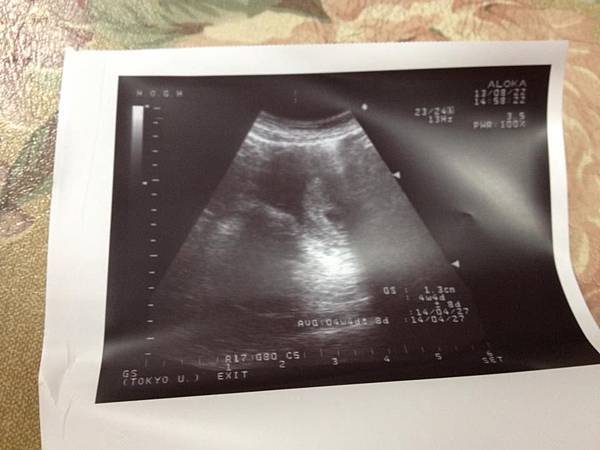

• 9月 11 週三 201311:59

1234591_10201768014351894_723686032_n.jpg4w4d.jpg8w2d-1.jpg8w2d-2.jpg

(繼續閱讀...)